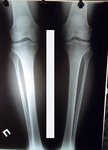

ножки в аппаратах, в день снятия.